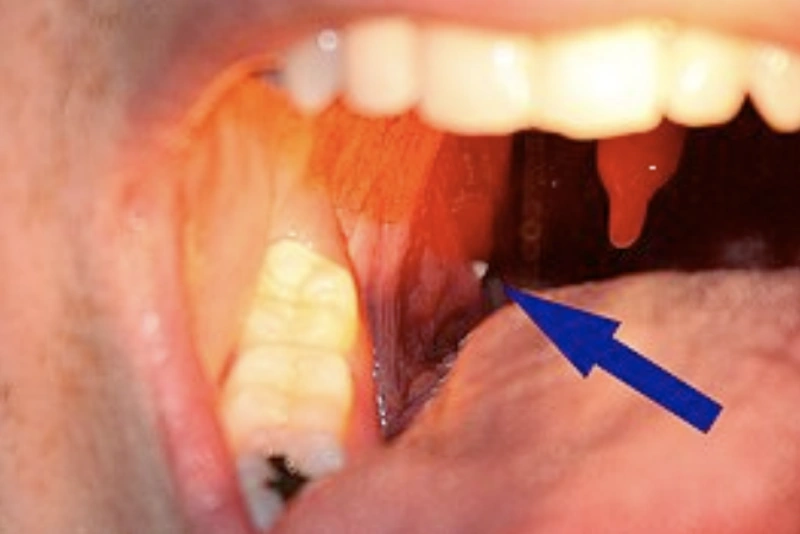

Os cáseos amigdalianos são pequenas formações sólidas que se desenvolvem nas amígdalas, estruturas localizadas no fundo da garganta que fazem parte do sistema imunológico.

Eles são formados pelo acúmulo de restos de alimentos, células mortas da mucosa bucal, bactérias e muco. Quando esse material fica preso nas criptas amigdalianas, o cálcio presente na saliva endurece a massa, criando as chamadas “pedrinhas”.